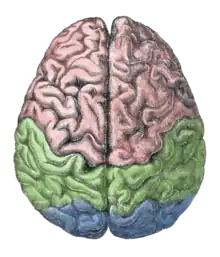

The pursuit rotor task is a simple pure visual-motor tracking test that has consistent results within age groups.[20] This displays a measurement of procedural memory as well as demonstrates the participant's fine motor skills. The pursuit rotor task tests the fine-motor skills which are controlled by the motor cortex illustrated by the green section below.